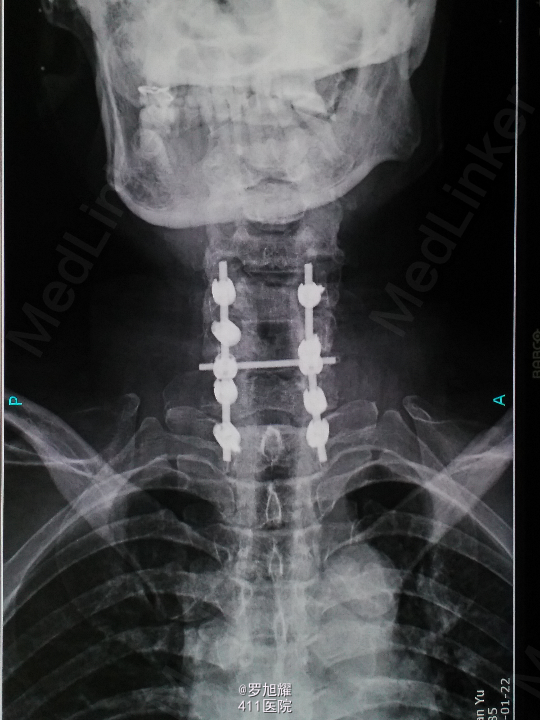

查体:双上肢前臂及以远感觉丧失,躯体自第二肋间平面以下感觉丧失。耸肩可,双侧三角肌、肱二三头肌肌力2级,腕关节屈伸、旋转及各指肌力0级。腱反射阴性,但球海绵体反射已经阳性。影像学检查示颈椎骨折脱位伴颈髓损伤。

诊断:颈6/7骨折脱位伴高位截瘫。处理:立即甲强龙冲击、脱水、保胃、营养神经治疗。首选治疗方案是颅骨牵引复位后前路融合固定,较后路稳定,出血也少,和家属谈话后开始颅骨牵引复位,4kg起步,每半小时增加1kg直至14kg,调整颈椎屈伸位,再加用手法牵引仍不能复位。改用备选方案,急诊行后路切开减压撬拨复位内固定,术后瘫痪症状部分改善。随访3月双上肢前臂及手部感觉恢复,仅双手掌尺侧及小指感觉障碍,双侧三角肌、肱二三头肌肌力4-5级,腕关节屈伸、旋转肌力左侧3级,右侧3-4级,但各指肌力仍0级。